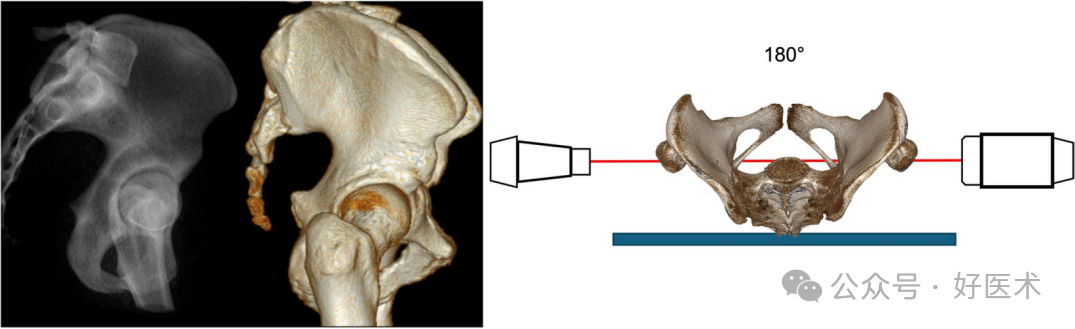

真正的侧视图(TLV)

TLV显示两侧半骨盆重叠。与X线照射器一侧的半骨盆相比,更接近X线接收器的半骨盆投影更小。两侧坐骨大切迹线和髂骨皮质重叠是获得**视野的先决条件。此外,两个髋臼圆应相互重叠(图11)。

图 11 坐骨大切迹线与髂骨皮质重叠的真实侧视图 (TLV)